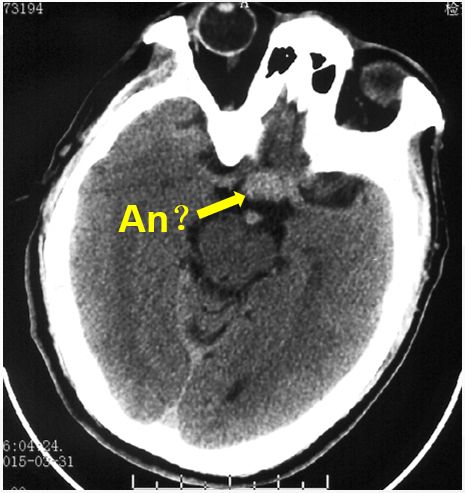

术前头颅CT检查(发病6天后)

头颅CT可见鞍区类圆形高密度影

(黄色箭头示)